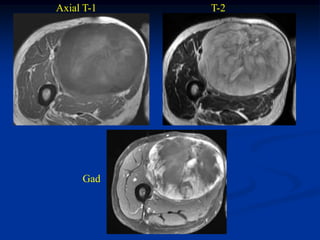

Case #259                   Axial T-1 MRI

72 year male with MFH posterior compartment thigh

Axial T-2 MRI